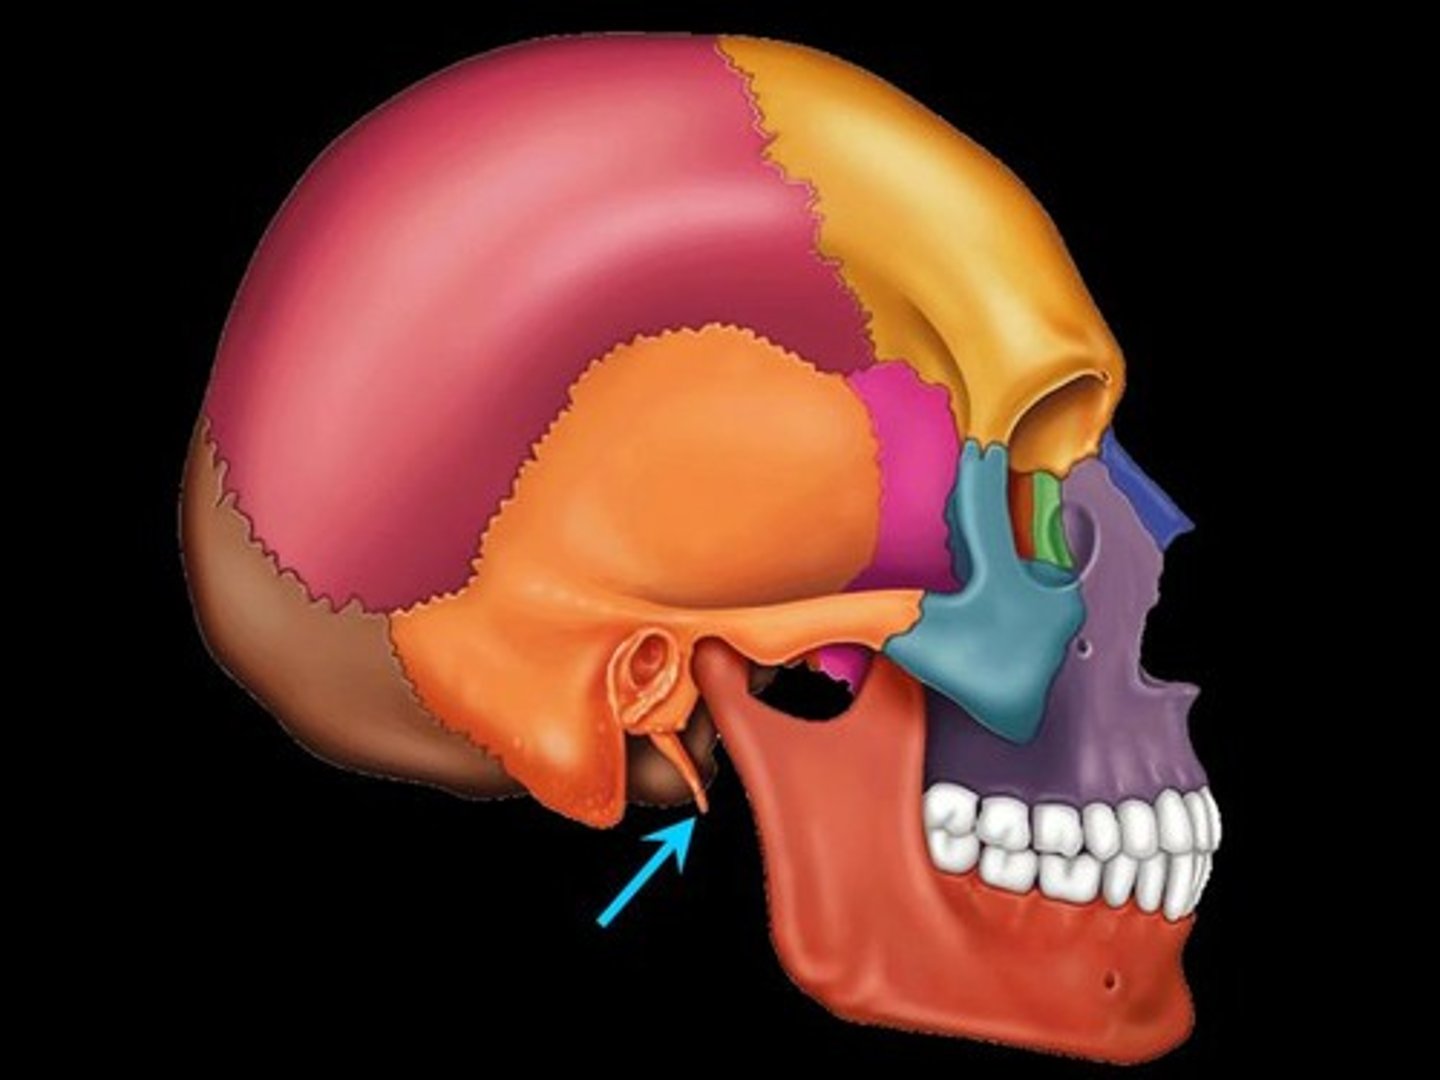

Mastoid Process

Round projection on the temporal bone behind the ear

Styloid Process

Pole-like process extending downward from the temporal bone on each side of the skull

Stylomastoid Process